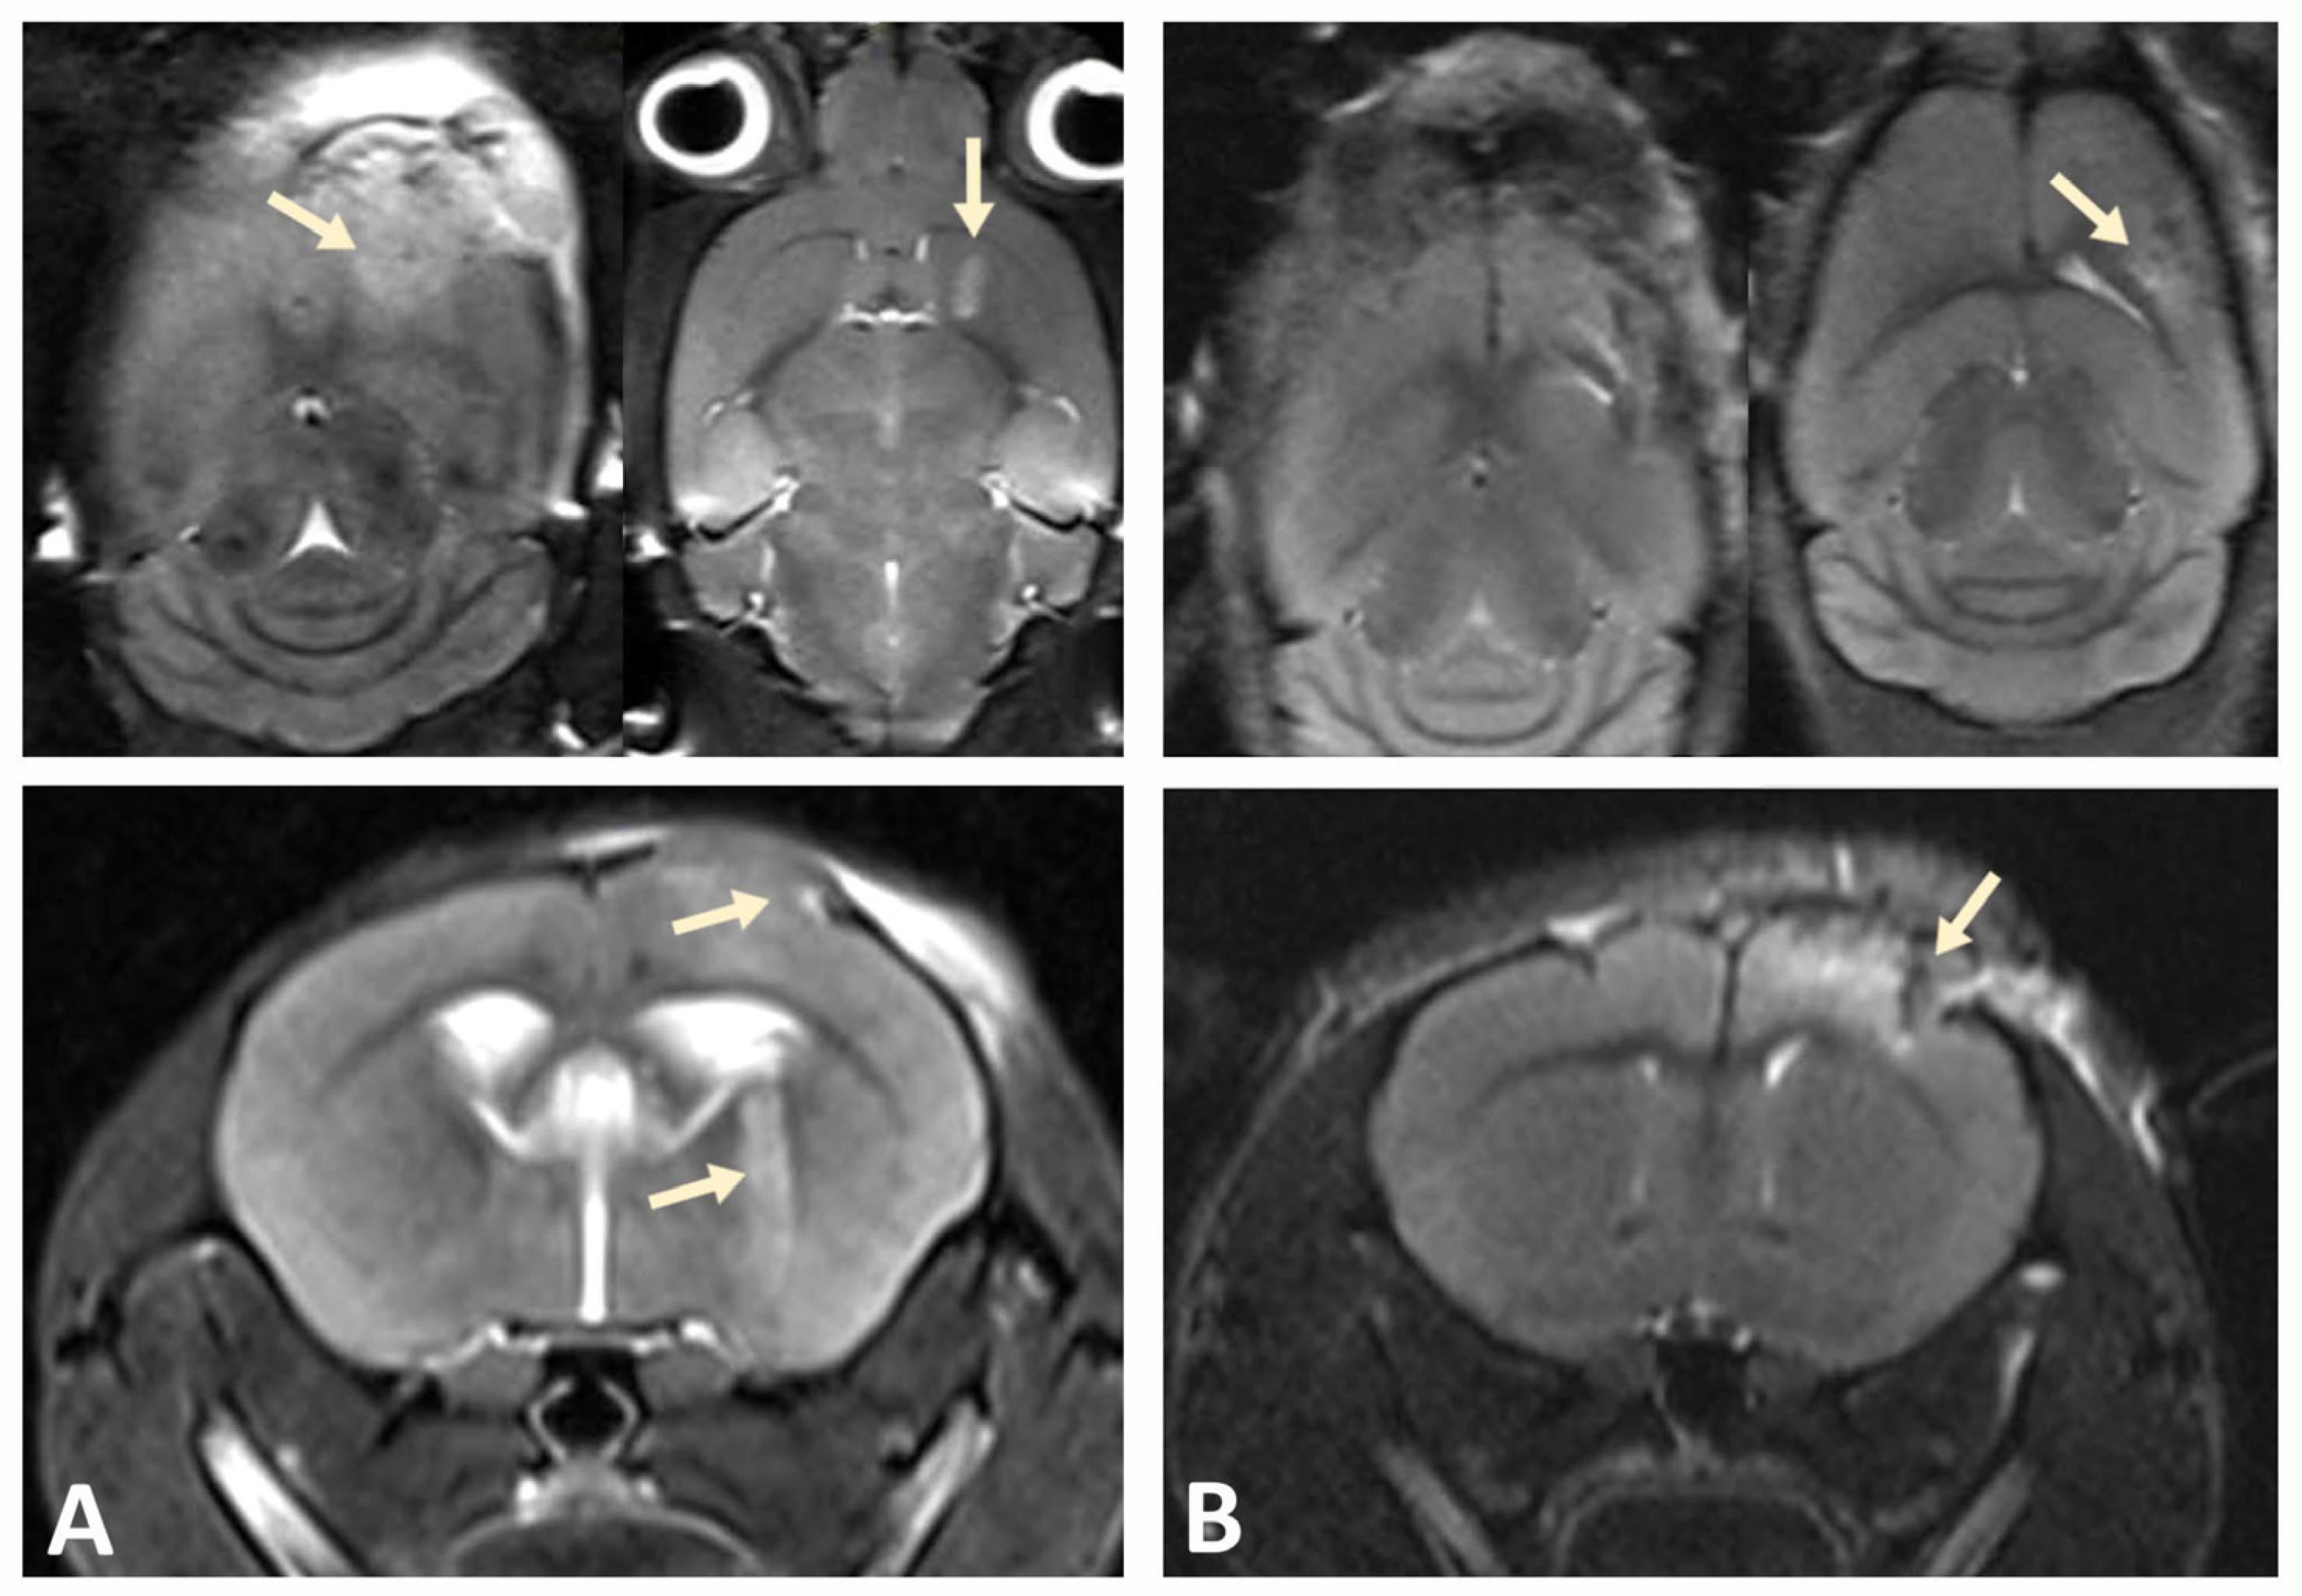

3.2. MRI Confirms Successful Engraftment of Human GBM PDX Cells in the Brain of NSG Mice

A xenograft model was developed by stereotactic implantation of a suspension of glioblastoma (GBM) cells into the striatum of the right hemisphere of immunodeficient NSG mice. The MRI was used to assess tumor growth at the injection site and GBM cell migration after implantation in a mouse brain to validate successful establishment of the xenograft model. Scanning was performed in three projections to determine the direction of tumor cell migration within the mouse brain tissue. Tumor growth was observed in the injection zone, which confirmed the successful engraftment of human GBM xenograft cells and corresponded to the expected parameters of the model (Figure 3).

Figure 3.

Tumor progression monitored by MRI. (A) On day 10, pronounced cortical growth of glioblastoma and a focus in the subcortical ganglia (indicated by arrows) were observed. (B) Implantation of GBM cells into the cortex of the hemispheres of NSG immunodeficient mice at the same time point was characterized by smaller tumor size.